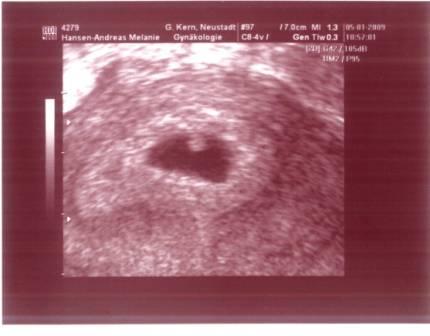

Montag den. 05.01.2009: Bin

morgens gleich zu meiner Ärztin und wurde glücklicherweise am späten

Vormittag auch ohne echten Termin dazwischengeschoben. Meine Ärztin war ganz

überrascht, weil ich im Oktober das letzte Mal zur Kontrolle dagewesen bin,

und ich da über schwankenden Zyklus klagte, welches den Kinderwunsch nicht

gerade einfacher macht. So freute Sie sich für uns, dass es doch geklappt

hatte. Dann kam der große Moment. Ich war so hibbelig, weil ich ja die ganze

Zeit Angst hatte, es könnte sich noch um eine Eileiterschwangerschaft

handeln. Doch da war es in diesem Kasten. Unser kleines Böhnchen. Zu dem

Zeitpunktwirklich nicht anders zu benennen, aber das Herz schlug schon wie

wild und die Gefühle bei dem Anblick, waren unbeschreiblich. Die Ärztin war

zufrieden und wir machten einen Termin für Anfang Februar aus. Dann sollte

ich auch meinen Mutterpass bekommen und die Blutuntersuchung gemacht werden.

Hier das erste Bild unseres Böhnchens. Das war SSW 6+1. Oder wie mein